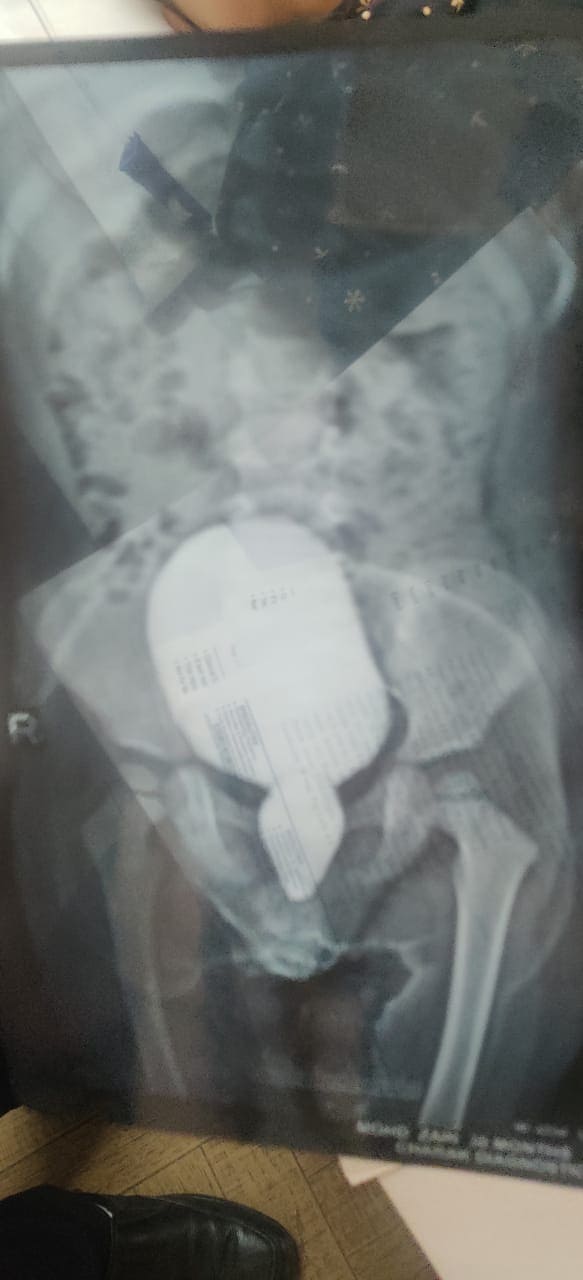

Anorectal malformation with scrotal fistula with bifid scrotum

Creat neoanus with improvement of scrotal appearance as normal